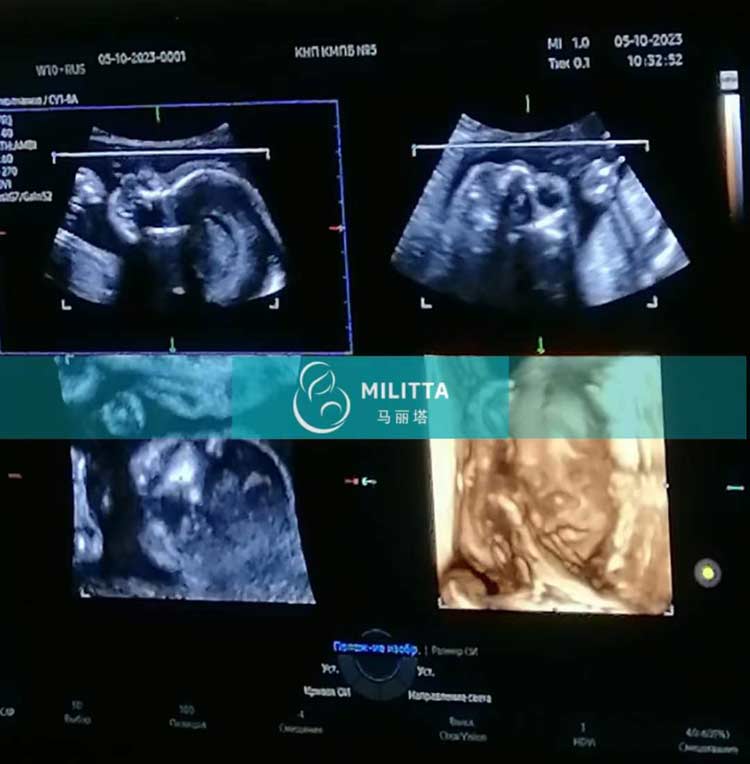

格鲁吉亚助孕L夫妇的乌克兰试管妈妈在妇产医院做四维彩超产检

安排选择格鲁吉亚助孕L夫妇的乌克兰试管妈妈在妇产医院做四维彩超产检,经检查胎儿身体发育很好,得知结果的妈妈也露出了满意的笑容,很快就要到第比利斯待产咯